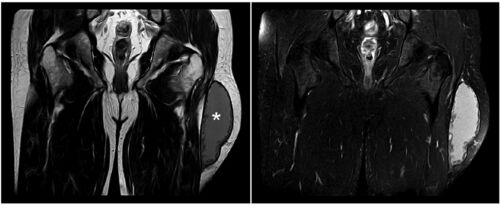

case148:左大腿部の腫脹と疼痛を訴える57歳男性(Ann Emerg Med. 2021 Jun;77(6):e117-e118.)

コレ自体は救急外来で見たら、 「後日整形外科で精査してもらってください」系の疾患かもしれません。 でも大腿部だけではなくて体のさまざまな部位に発生するようなのでコレを知っておくと汎用性が高いかも⁉ 病歴/身体所見 ・57歳男性 ・2か月前からの左大…